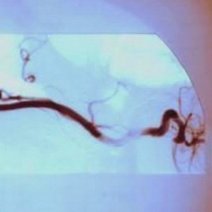

- 数字减影血管造影技术,颅内动脉瘤介入治疗,湘雅护理学院,颅内动脉瘤,颅内动脉瘤系指脑动脉壁的异常膨出部分,是引起自发性蛛网膜下腔出血的最常见原因。病因-尚不甚清楚,但以先天性动脉瘤占大部分。任何年龄可

- 颅内动脉瘤介入治疗的护理,主讲人杨鑫,。,一、概述颅内动脉瘤时由于局部血管异常改变产生的脑血管样突起。其主要症状多由出血引起,部分因瘤提压迫,动脉痉挛及栓塞造成。,,,,,,,,,,,,二、颅内动脉瘤介入适应症和禁忌症适应症、几乎所有的动脉

- 动瘤DavidSLiebeskind1引1.1景动瘤是有破倾向的管结构的病理性局灶性扩张。些管异常常根据假定的病因分类。囊状、浆果状或先天性动瘤占全动瘤的90